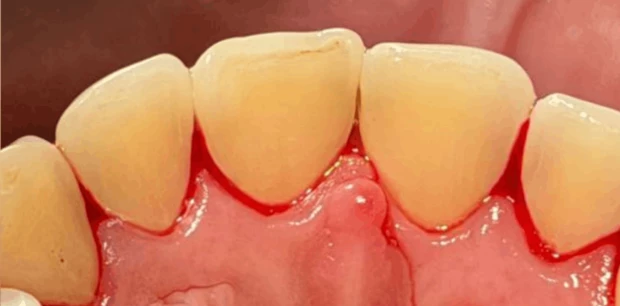

Профгигиена

Профессиональная гигиена зубов

Пациент Ф., 27 лет обратился с жалобами на периодическую кровоточивость десен при чистке зубов и на скученность зубов. Проведена профессиональная гигиена полости рта, пациент направлен на ортодонтическое лечение.